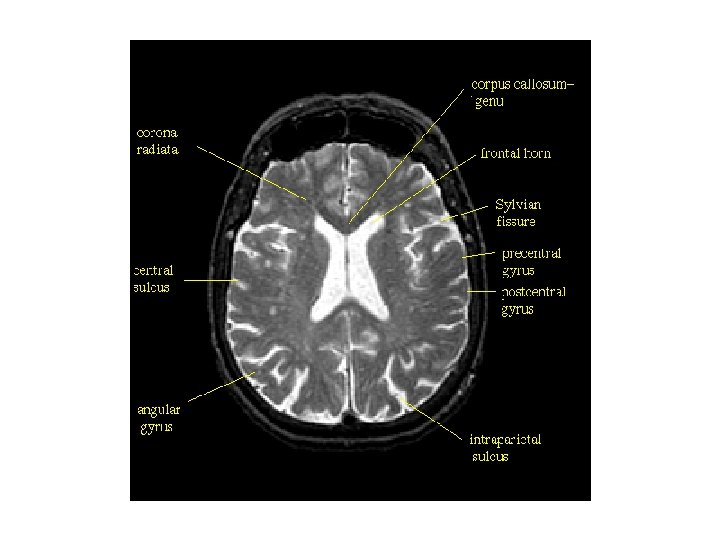

대뇌 외측표면에서 관찰되는 구조 1. 외측고랑(lateral fissure) 3. 하전두이랑 안와부(pars orbitalis) 5. 하전두이랑 삼각부(pars triangularis) 7. 하전두이랑 판개부(pars opercularis) 9. 상전두이랑(superior frontal gyrus, 상전두회) 11. 상전두고랑(superior frontal sulcus, 상전두구) 13. 중심전이랑(precentral gyrus, 전중심회) 15. 중심후이랑(postcentral gyrus, 후중심회) 17. 두정엽내고랑(intraparietal sulcus) 19. 변연상이랑(supramarginal gyrus, 연상회) 21. 두정후두고랑(parieto-occipital sulcus) 23. 외측후두이랑(lateral occipital gyrus) 25. 외측고랑 뒷가지(posterior ramus, 후지) 27. 하측두이랑(inferior temporal gyrus) 29. 상측두고랑(superior temporal sulcus) 31. 측두극(temporal pole) 2. 전두극(frontal pole) 4. 외측고랑 앞가지(anterior ramus, 전지) 6. 외측고랑 오름가지(ascending ramus, 상행지) 8. 하전두고랑(inferior frontal gyrus, 하전두구) 10. 중간전두이랑(middle frontal gyrus, 중전두회) 12. 중심전고랑(precentral sulcus, 전중심구) 14. 중심고랑(central sulcus, 중심구) 16. 중심후고랑(postcentral sulcus, 중심후구) 18. 상두정소엽(superior parietal lobule) 20. 각이랑(angular gyrus, 각회) 22. 후두극(occipital pole) 24. 후두전패임(preoccipital notch) 26. 하측두고랑(inferior temporal sulcus) 28. 중간측두이랑(middle temporal gyrus) 30. 상측두이랑(superior temporal gyrus)

내섬유막(internal capsule)과 피질척수로(corticospinal tract). 왼쪽 피라미드로(pyramidal tract) 의 섬유다발을 해부하여 그 경로를 나타내었다. 1. 대상고랑(cingulate sulcus) 2. 대상이랑(cingulate gyrus) 3. 중심전이랑(precentral gyrus) 4. 두정후두고랑(parietao-occipital sulcus) 5. 쐐기소엽(cuneus) 6. 새발톱고랑(calcarine sulcus) 7. 시각로(optic tract) 8. 외측무릎체(lateral geniculate body) 9. 중소뇌각(middle cerebral peduncle) 10. 올리브(olive) 11. 피라미드(pyramid) 12. 시각신경교차(optic chiasm) 13. 내섬유막(internal capsule) 14. 뇌량무릎(genu of corpus callosum)